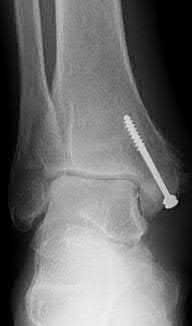

A 28-year-old male sustains a severe hyper-dorsiflexion injury to his ankle in a motor vehicle accident, resulting in a Hawkins Type III talar neck fracture. Which of the following arteries provides the predominant blood supply to the body of the talus, placing it at significant risk for avascular necrosis in this injury?

Correct Answer: Artery of the tarsal canal

Explanation:

The artery of the tarsal canal, which is a branch of the posterior tibial artery, provides the dominant blood supply to the talar body. In a Hawkins Type III fracture (talar neck fracture with subtalar and tibiotalar dislocation), the blood supply from the artery of the tarsal canal, the artery of the sinus tarsi, and capsular vessels are disrupted, leading to an avascular necrosis (AVN) rate approaching 100%.